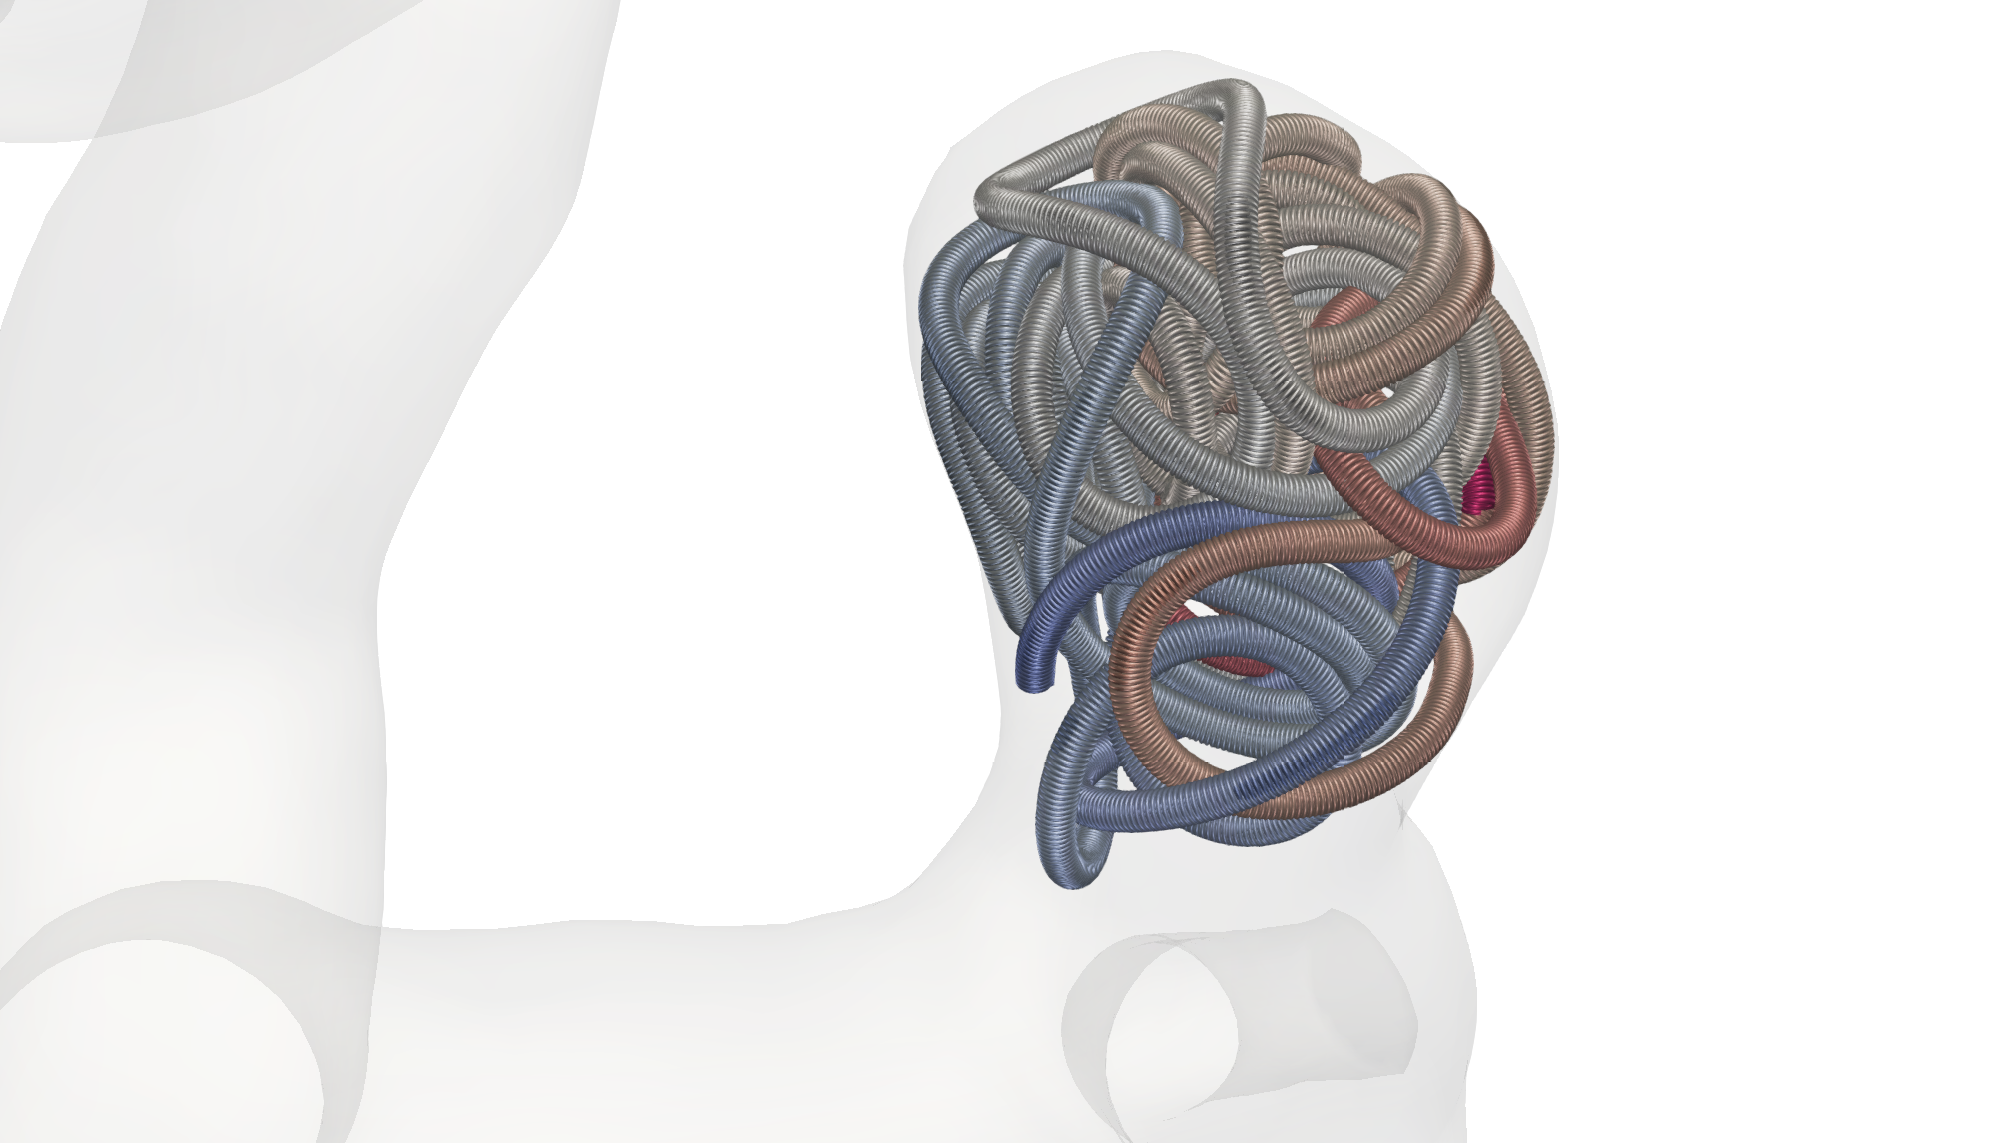

The coiling procedure is conducted under continuous imaging supervision in digital subtraction angiography, a fluoroscopy technique, where an interventionist inserts a catheter through a femoral or radial access to reach for the brain along the upstream of blood, carefully moving to the part where the aneurysm is located. Then, via a micro-catheter, the wire is protruded into the aneurysm dome. Coils do exist in various shapes and sizes as well as with various material properties [23, 27, 51]. A patient-specific choice, e.g., with respect to the length or the imprinted natural shape of the inserted coil(s), is made based on preceding aneurysm measurements as well as the surgeons experience with respect to optimal placement [32]. Possible choices are, e.g., a stiffer framing coil followed by one or several softer filling and finishing coils depending on the shape of the aneurysm, see Fig. 1.

with denoting the coefficients of stick and slip friction, and being the threshold that decides when the model switches between stick and slip friction. All in all, our forces are thereby given as . To conclude this section, we assume that the micro-catheter is modeled as a cylindrical surface without lids following a spline curve that is generated by 3 points in space. By triangulating its surface, we can consider it as rigid object and model its collisions with the coil in the same ways as done in (20). This concludes our discussion of the model we use of the endovascular coil embolization. An example for a embolized coil in the small aneurysm is given in Fig. 8. Here (8(a)), (8(b)) show side views. The view (8(c)) is from bottom, looking through the aneurysm neck into the aneurysm.